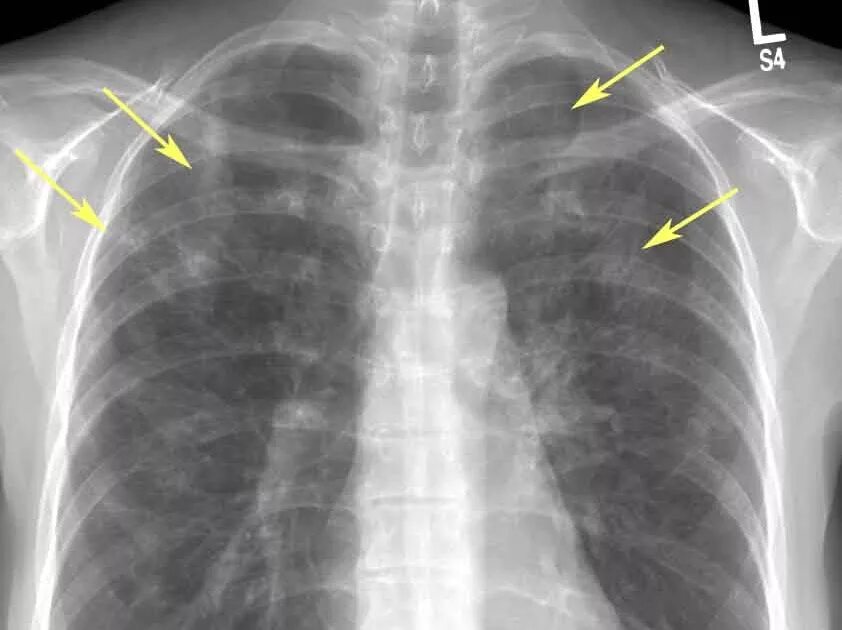

Скате легких